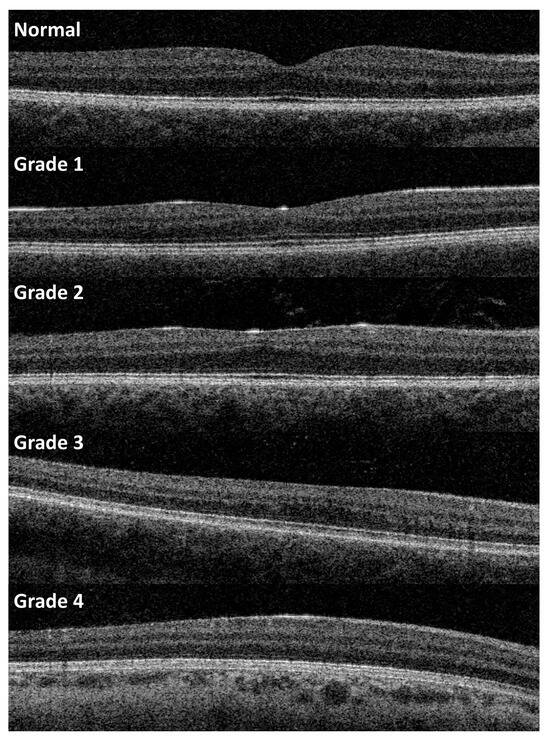

- Thomas, M.G.; Kumar, A.; Mohammad, S.; Proudlock, F.A.; Engle, E.C.; Andrews, C.; Chan, W.-M.; Thomas, S.; Gottlob, I. Structural Grading of Foveal Hypoplasia Using Spectral-Domain Optical Coherence Tomography a Predictor of Visual Acuity? Ophthalmology 2011, 118, 1653–1660. [Google Scholar] [CrossRef]

- Rufai, S.R.; Thomas, M.G.; Purohit, R.; Bunce, C.; Lee, H.; Proudlock, F.A.; Gottlob, I. Can Structural Grading of Foveal Hypoplasia Predict Future Vision in Infantile Nystagmus?: A Longitudinal Study. Ophthalmology 2020, 127, 492–500. [Google Scholar] [CrossRef]